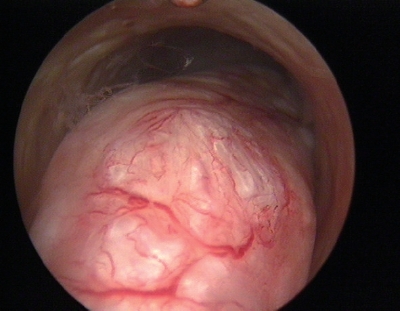

7)子宫内膜癌:病灶局限或扩散、向内或向外生长,可表现为息肉型、结节型、乳头型或溃疡型,表面异形血管爬行,常伴有坏死、感染和出血(图3-17)。